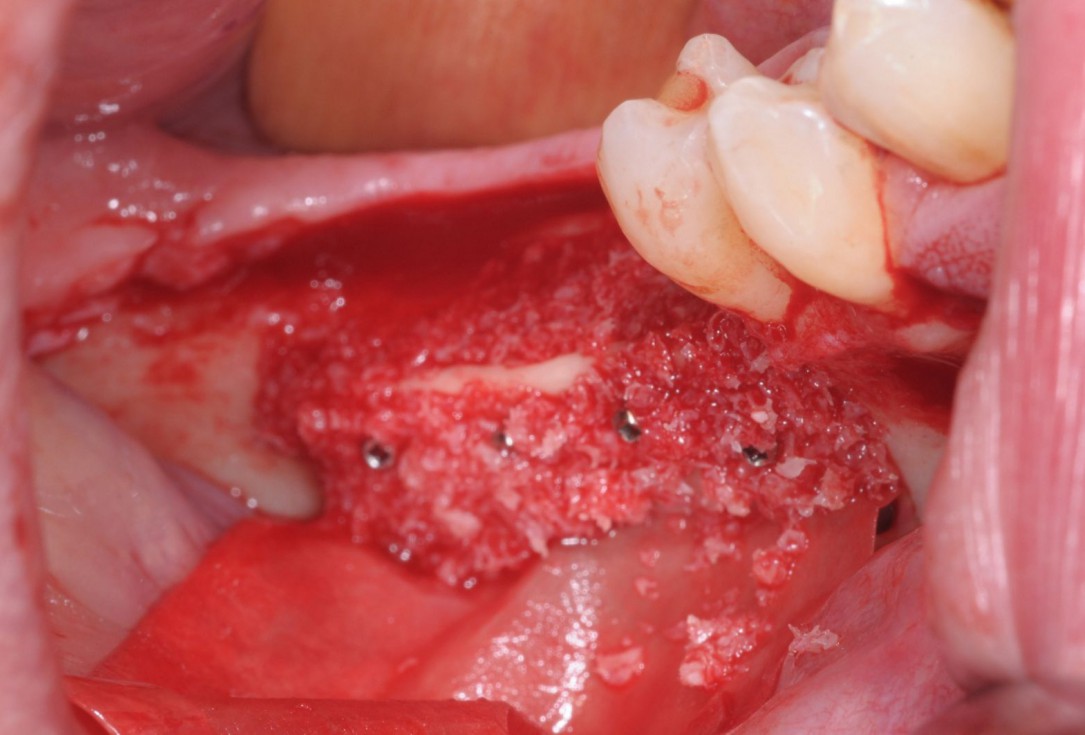

08/28 - Defect-fill and contouring with a composite of autologous and allogenic maxgraft® granules and covering with Jason® membraneThree-dimensional augmentation with maxgraft® cortico - Dr. R. Würdinger